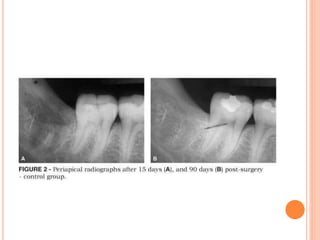

 Much of this early bone is poorly calcified, as is evident from

its general radiolucency on the radiograph.

 Radiographic evidence of bone formation does not become

prominent until the sixth or eighth week after tooth extraction.